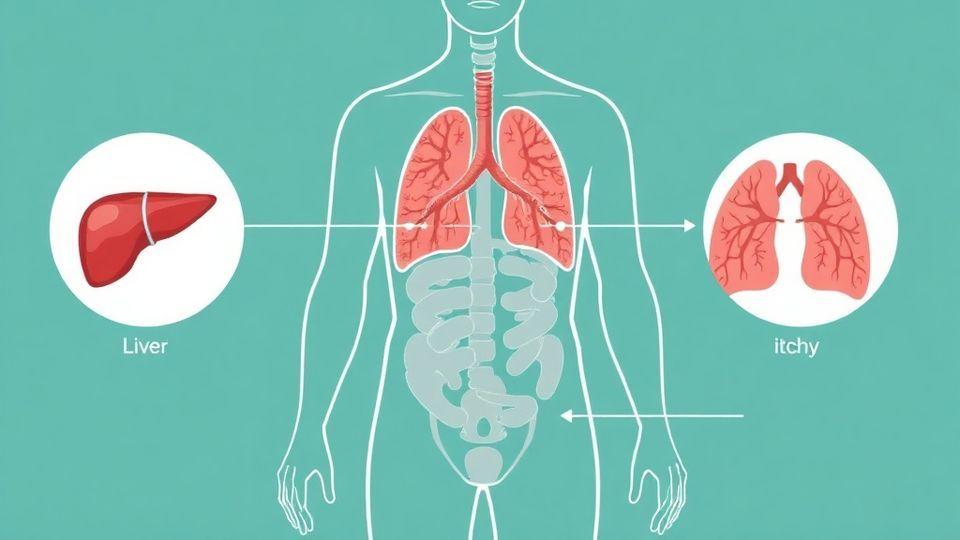

🔍 간, 신장, 폐의 가려움증 경고 신호

손바닥과 발바닥이 속에서부터 뜨겁게 가렵고 밤에 심해진다면 간과 담도 문제를 의심해보셔야 합니다. 양쪽 정강이와 발목이 대칭적으로 가렵고 소변에 거품이 생긴다면 신장 건강을 점검해야 합니다. 등 상부가 활동할 때 더 심하게 가려운 경우에는 폐의 신경이 자극받고 있을 가능성이 있습니다. 📈